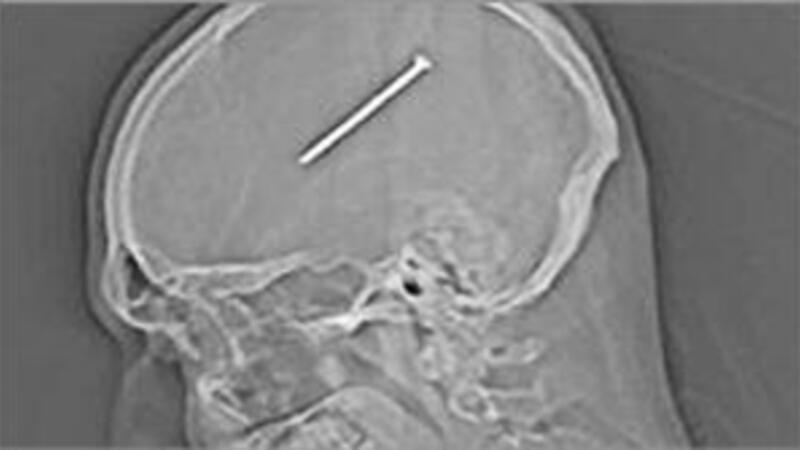

المسمار داخل الراس

تمكن جراحون من اخراج مسمار بطول 8.25 سنتيمتر من وسط دماغ شخص من ضواحي شيكاغو، ضرب نفسه عرضا به.

وكان المصاب دانتي اوتيلو (34 عاما) يعمل في ورشته عندما ضغط عرضا على زر مسدس لتثبيت المسامير قرب رأسه، غير ان ما كان يجهله دانتي ان المسمار دخل رأسه، ولم يشعر بذلك حتى اليوم التالي عندما بدأ يعاني نوبات ترنح وعدم توازن.

وقال الاطباء لدانتي «ان المسمار كان على بعد ملليمترات فقط من منطقة حساسة جدا وسط الدماغ مسؤولة عن فعاليات حيوية مهمة».